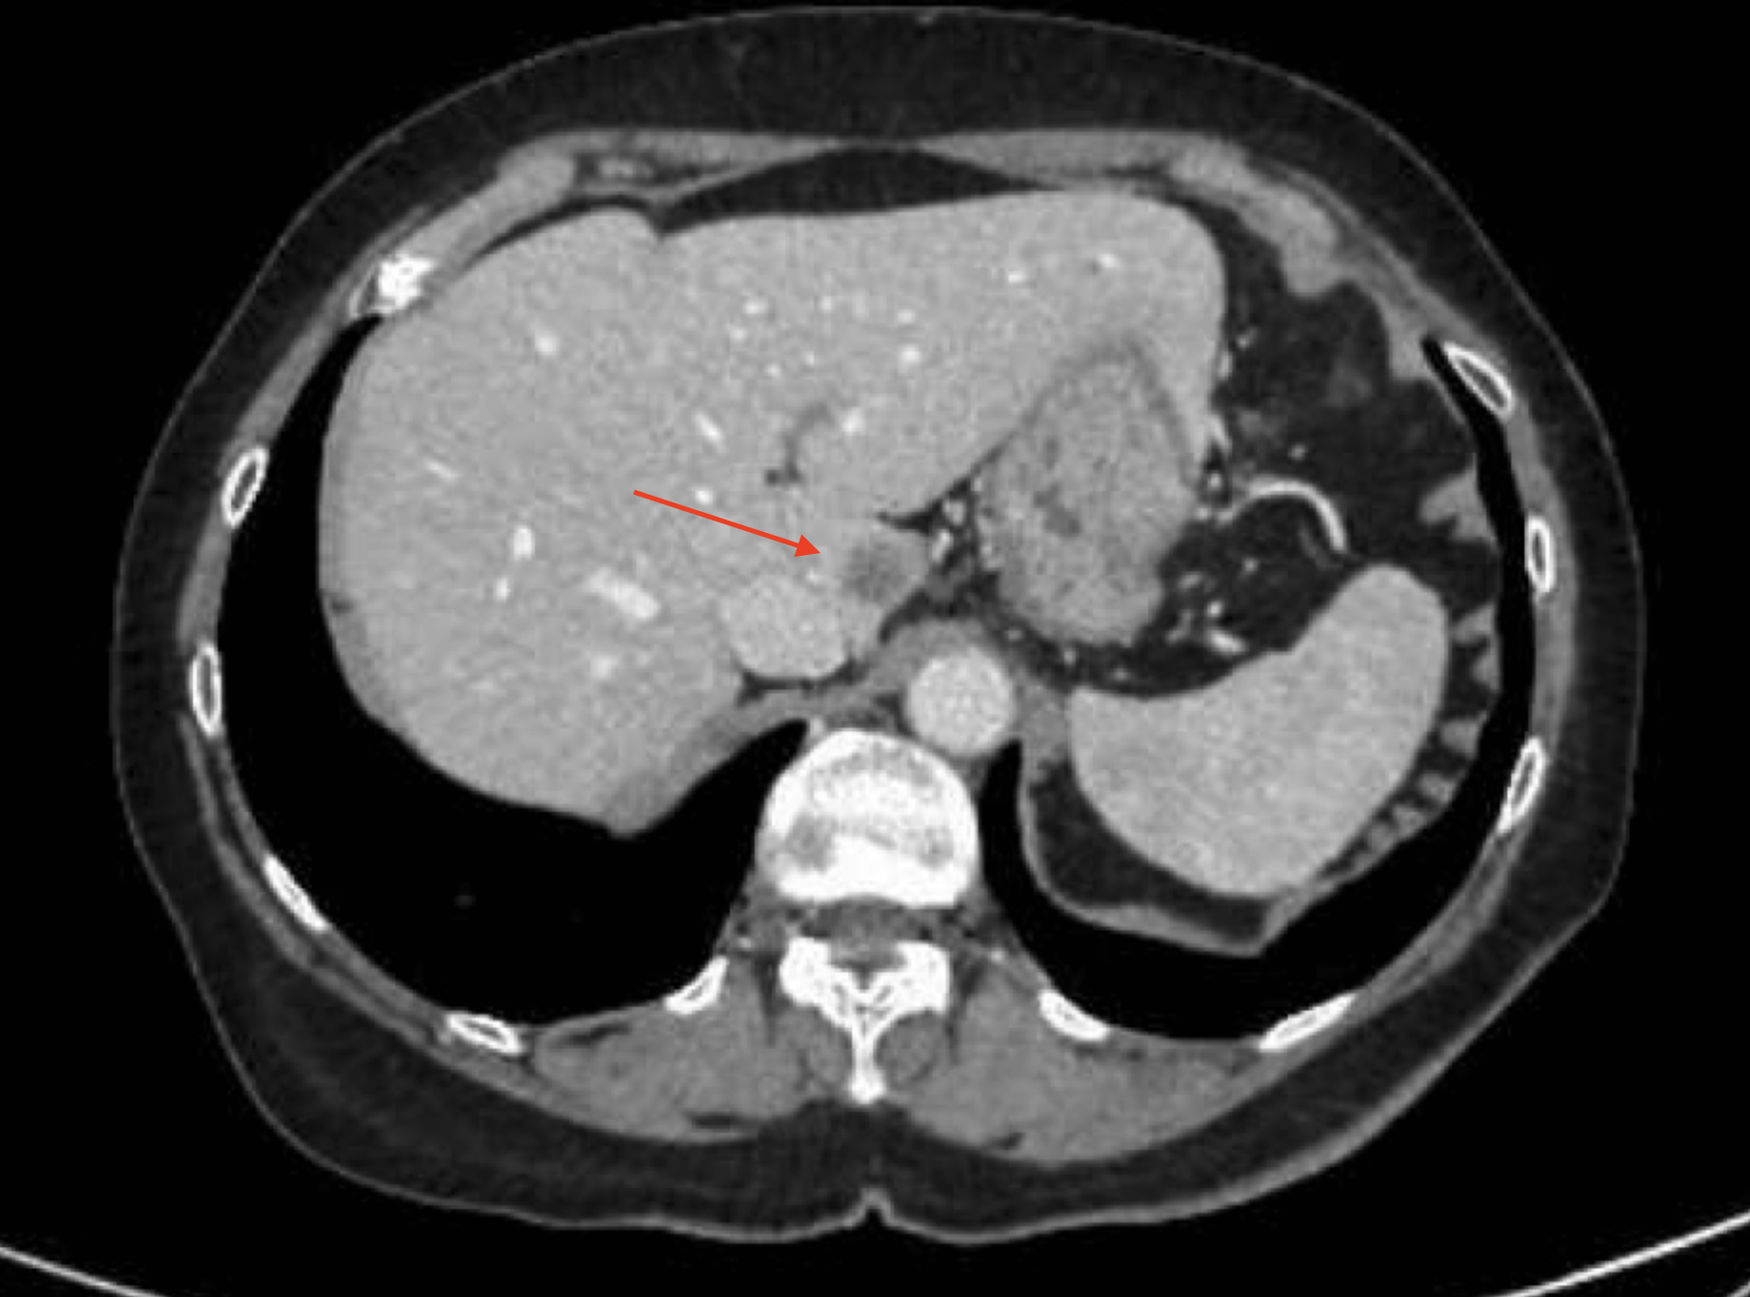

Presentamos el caso de una mujer de 72años a la que se le realizó una hemicolectomía derecha laparoscópica en septiembre de 2022. El CEA subió a 10,8, por lo que se realizó una TAC y una RM, que mostraron una metástasis en el segmentoI hepático, por lo que se propuso una resección hepática robótica del segmentoI mediante el sistema Da Vinci Xi.

El abordaje robótico para la resección del segmento hepáticoI en casos seleccionados es un procedimiento seguro que ofrece una excelente visualización del área quirúrgica, lo que facilita una intervención rápida y con mínimo sangrado, siempre que sea realizado por cirujanos experimentados en técnicas hepáticas mínimamente invasivas (fig. 1).